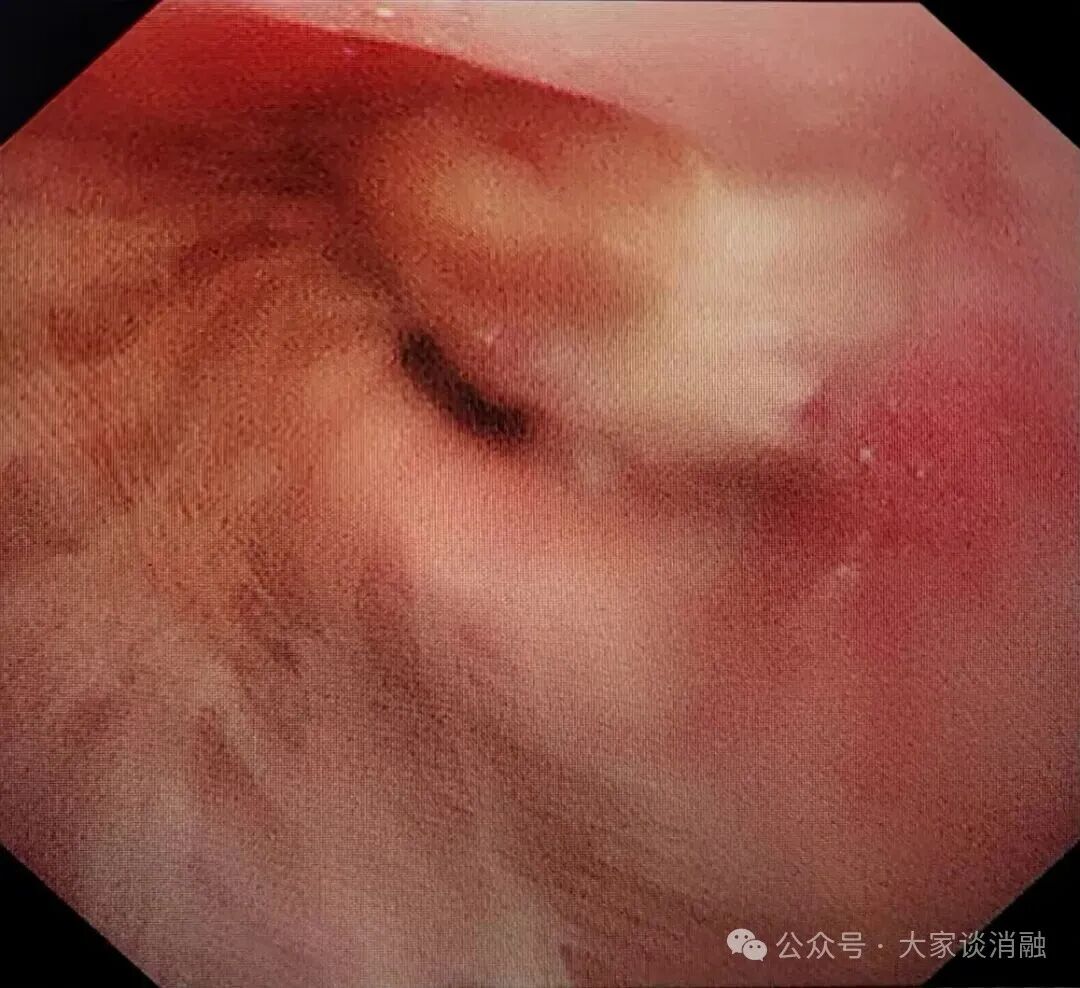

第一次治疗

10月22日,患者接受第一次PTS治疗,在呼吸内二科邵桂英主任的精细操作下,全程顺利治疗后气道内肿瘤缩小达30%,患者呼吸困难症状大大缓解。

术前